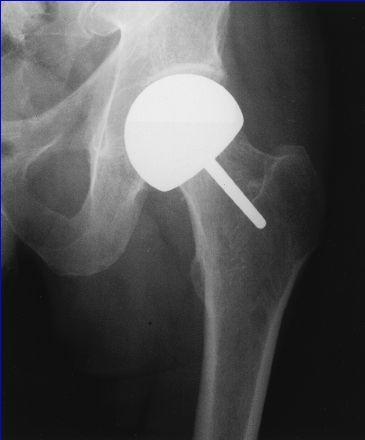

Artroplastia Femoral de Revestimiento

Limitada

Artroplastia Femoral de Revestimiento Limitada Este procedimiento cuenta con algunas ventajas:  (1) se extirpa el cartílago dañado de la cabeza femoral,  (2) preserva la reserva ósea de la cabeza y cuello femorales y  (3) la revisión a una artroplastia total subsiguiente no se complica.

Artroplastia Total de Cadera

Artroplastia Total de Cadera indicaciones  osteonecrosis de la cabeza femoral con cambios y lesión severa del cartílago articular de la cabeza y pérdida del cartílago acetabular.  con afectación extensa o colapso de la cabeza femoral que tiene síntomas suficientes.  Pacientes mayores o con bajas demandas funcionales.